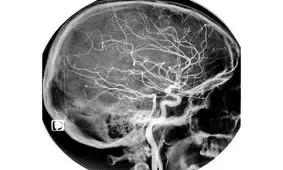

پژوهشگران آمریکایی، نوعی اطلس سلولی ابداع کردهاند که ممکن است بتواند به ارائه درمان مناسب برای سکته مغزی و زوال عقل…